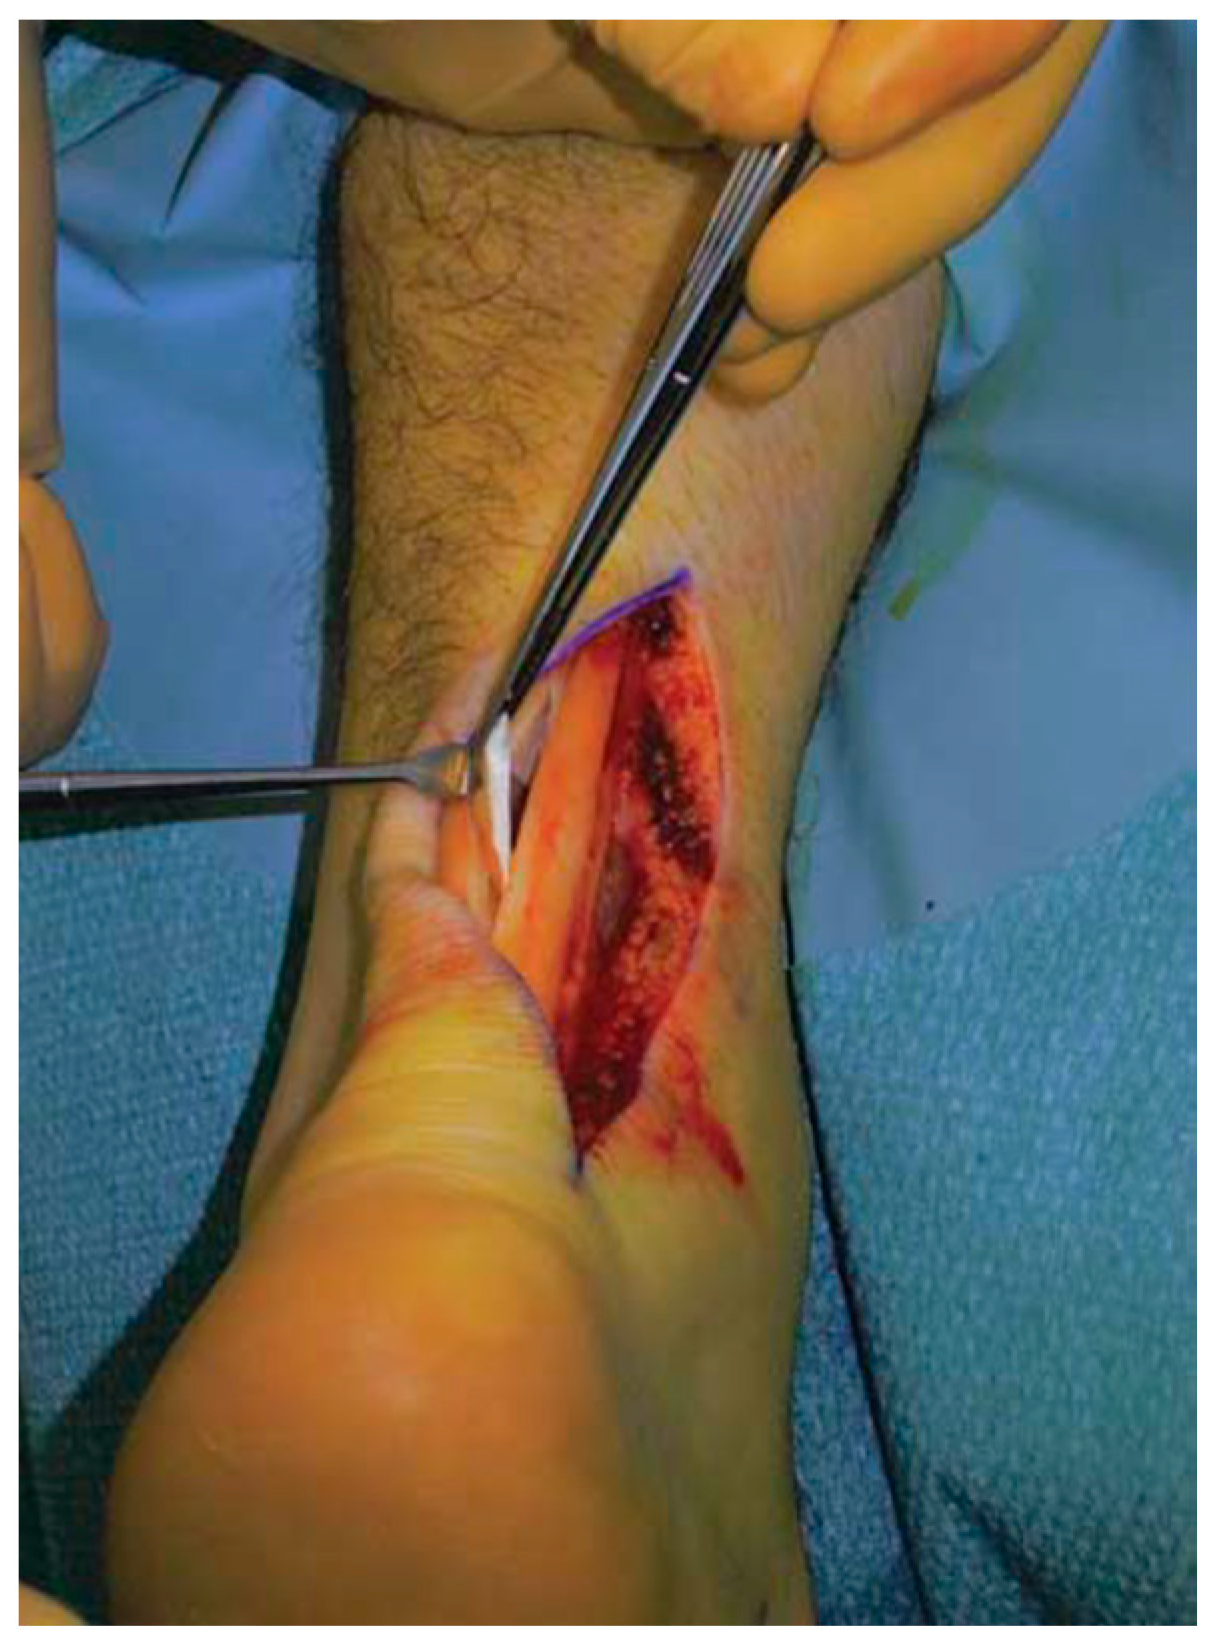

3.4.1. Open Surgery for AT

- Maffulli, N.; Binfield, P.M.; Moore, D.; King, J.B. Surgical Decompression of Chronic Central Core Lesions of the Achilles Tendon. Am. J. Sports Med. 1999, 27, 747–752. [Google Scholar] [CrossRef] [PubMed]